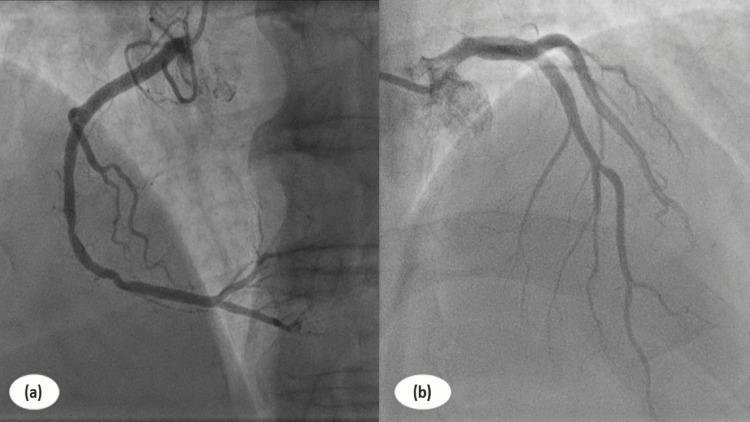

急性胰腺炎是一种伴有不同局部和全身并发症且严重程度各异的炎症性疾病。虽然罕见,但急性胰腺炎引发的心血管并发症在文献中鲜有描述。急性胰腺炎所致的上腹部疼痛在无冠状动脉异常时常常类似心电图改变,这给最佳治疗和管理带来了诊断难题。我们着重介绍一例急性胰腺炎合并急性冠状动脉综合征的病例,该患者表现为胸部闷痛、呼吸困难、恶心,以及伴有呕吐的上腹部疼痛加重。临床和实验室评估以及影像学检查提示,在无冠状动脉异常的情况下,急性胰腺炎酷似心肌梗死(MI)。